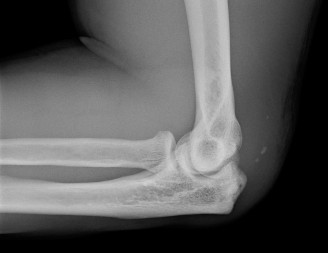

The correct answer is (B). A pectoralis major muscle (PMM) tear or rupture usually occurs in weight-lifters while performing the bench press, but it can occur during

any activity in which the arm is extended and externally rotated while under maximal contraction (eccentric loading force). Patients often present with pain, swelling, ecchymosis, weakness and loss of the axillary fold in the acute setting. In the chronic setting, the swelling and ecchymosis have typically subsided. They may report an audible pop or a tearing sensation. On examination, there can be an apparent continuous muscle or tendon that is mistaken for an intact PMM tendon, but this represents the fascia of the PMM that is continuous with the fascia of both the brachium and the medial antebrachial septum. This continuous fascia will examine as a cord-like structure as shown in Figure 2–78.

Figure 2–78